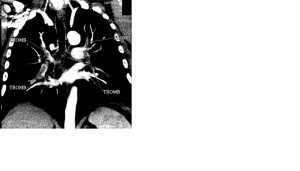

Для окончательной верификации диагноза (так как состояние пациента оставалось гемодинамически стабильным) была проведена мультиспиральная компьютерная томография (мсКТ), которая подтвердила наличие ТЭЛА и выявила множественные тромбы в основных ветвях обеих легочных артерий (ри.3. МсКТ при поступлении).

Рис. 3. Данные мсКТ с контрастированием сосудов малого круга кровообращения (исходно и после проведения тромболитической терапии).

МсКТ при поступлении (13.02.13) МсКТ после проведения ТЛТ (18.02.13)

Б. Множественные тромбы в основных ветвях легочных артерий![]() |

Б. Единичные тромбы в субсегментарных ветвях легочных артерий![]() |